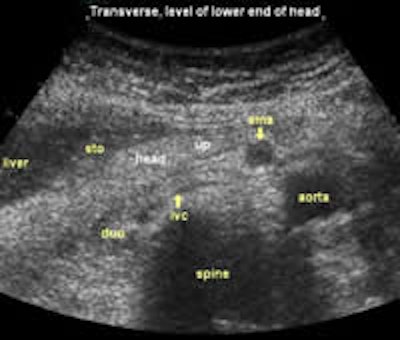

The following study describes anatomical landmarks in the ordinary pancreas of a thin patient:

Transverse planes in caudal direction: